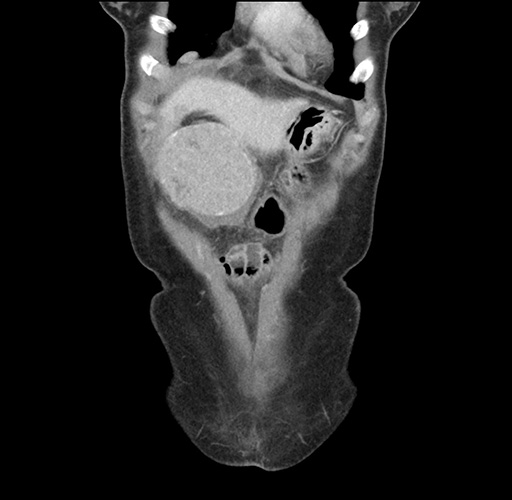

Imaging Analysis

Look through the patient's CT scan to identify any areas of concern for the necessary procedure.

Based on your CT findings, which issue(s) would give reason for "planned slowing down moment(s)" in this case?